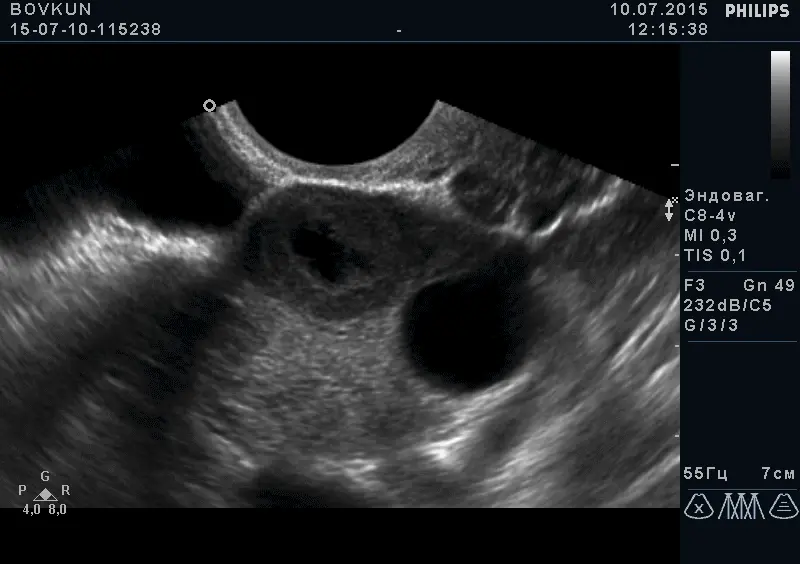

- Кісти яєчників

- Фолікулярний апарат яєчників

- Відслідковування овуляції, що використовується при проблемах з вагітністю, персистенції фолікулів і т.і.

Трансвагінальний доступ є “золотим стандартом” в дослідженні органів малого таза на увазі найкращою візуалізації з найтоншої оцінкою структури, оптимальний метод в діагностиці вагітності на ранніх термінах, оцінці будови плода до 14 тижнів. Датчик розташовується в піхві.

За допомогою УЗД можна побачити і оцінити стан тіла матки, шийки матки, яєчників, маткових труб (при їх патології) і оточуючих їх органів. Є пріоритетним методом дослідження стану судин малого таза. Під час дослідження вимірюються розміри всіх доступних для дослідження органів, оцінюється їх структура і відповідність фазі менструального циклу, оцінка кровопостачання органів і судин.